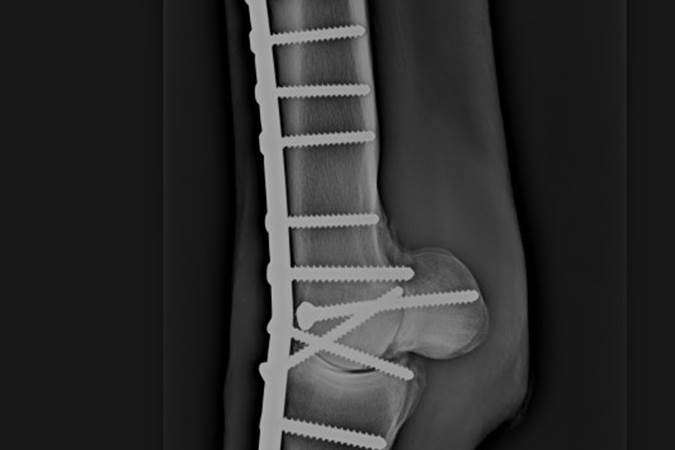

Arthrodesis – What Is It And When Can It Help?

Degenerative joint disease, or arthritis, is a common and debilitating condition in the horse which causes lameness and loss of performance.

Orthopaedic Surgery

Orthopaedics is the largest surgical discipline at NEH and concerns principally joints and bones, with the most common procedures including arthroscopic surgery and fracture repair.